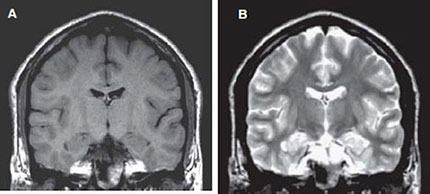

The pixel intensity in a MR image is a function of T1, T2 and image acquisition parameters (vide infra) such as TR (time of repetition) and TE (time of echo). In routine MRI, the images obtained are either PD, T1-weighted or T2-weighted. They usually do not refer to images that display PD, T1 or T2. Instead, the terms refer to the relative weight with which the three parameters affect the tissue contrast in MR images. Such images are obtained by varying the parameters TE and TR. Generally, tissues with short T1 will appear bright on T1- weighted image, and tissues with long T1 will appear dark. For example, in a T1- weighted image of the brain, the fat will appear as white; white matter as light gray and gray matter as gray and the CSF as black as shown in Figure 1.4A. In T2-weighted image of coronal section of the brain (Fig. 1.4B), fat appears as gray while the white matter as dark gray; the gray matter appears as gray and the CSF as white. T1-weighted images are useful for viewing the anatomy (morphology) while T2 images are useful for identifying the tissue pathology.

Figs 1.4A and B: Coronal SE MR images of a volunteer: (A) T1 – weighted [slice thickness = 5 mm; TR = 550 ms; TE = 15 ms; field of view (FOV) = 250 mm] and (B) T2- weighted (slice thickness = 5 mm; TR = 2600 ms; TE = 90 ms; FOV = 250 mm).